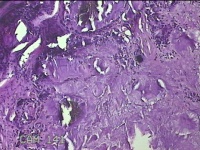

左外踝包块

性别

男

年龄

31岁

临床诊断

皮下结节

一般病史

发现左外踝包块1年余。

标本名称

大体所见

灰白暗红色包块1.8x1.3x0.7cm一个,表面糜烂,切开包块,内见大量石灰样物,内壁粗糙。

去了解病史,应该是痛风结节。